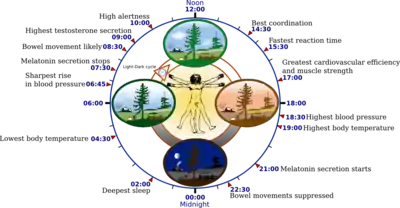

Circadian rhythm

Depression may be related to abnormalities in the circadian rhythm,[22] or biological clock.

A well synchronized circadian rhythm is critical for maintaining optimal health. Adverse changes and alterations in the circadian rhythm have been associated various neurological disorders and mood disorders including depression.[23]

Sleep disturbance is the most prominent symptom in depressive patients.[24] Studies about sleep electroencephalograms have shown characteristic changes in depression such as reductions in non-rapid eye movement sleep production, disruptions of sleep continuity and disinhibition of rapid eye movement (REM) sleep.[25] Rapid eye movement (REM) sleep—the stage in which dreaming occurs—may be quick to arrive and intense in depressed people. REM sleep depends on decreased serotonin levels in the brain stem,[26] and is impaired by compounds, such as antidepressants, that increase serotonergic tone in brain stem structures.[26] Overall, the serotonergic system is least active during sleep and most active during wakefulness. Prolonged wakefulness due to sleep deprivation[22] activates serotonergic neurons, leading to processes similar to the therapeutic effect of antidepressants, such as the selective serotonin reuptake inhibitors (SSRIs). Depressed individuals can exhibit a significant lift in mood after a night of sleep deprivation. SSRIs may directly depend on the increase of central serotonergic neurotransmission for their therapeutic effect, the same system that impacts cycles of sleep and wakefulness.[26]

Light therapy

Research on the effects of light therapy on seasonal affective disorder suggests that light deprivation is related to decreased activity in the serotonergic system and to abnormalities in the sleep cycle, particularly insomnia. Exposure to light also targets the serotonergic system, providing more support for the important role this system may play in depression.[27] Sleep deprivation and light therapy both target the same brain neurotransmitter system and brain areas as antidepressant drugs, and are now used clinically to treat depression.[28] Light therapy, sleep deprivation and sleep time displacement (sleep phase advance therapy) are being used in combination quickly to interrupt a deep depression in people who are hospitalized for MDD (major depressive disorder).[27]

Increased and decreased sleep length appears to be a risk factor for depression.[29] People with MDD sometimes show diurnal and seasonal variation of symptom severity, even in non-seasonal depression. Diurnal mood improvement was associated with activity of dorsal neural networks. Increased mean core temperature was also observed. One hypothesis proposed that depression was a result of a phase shift.[30]

Daytime light exposure correlates with decreased serotonin transporter activity, which may underlie the seasonality of some depression.[31]